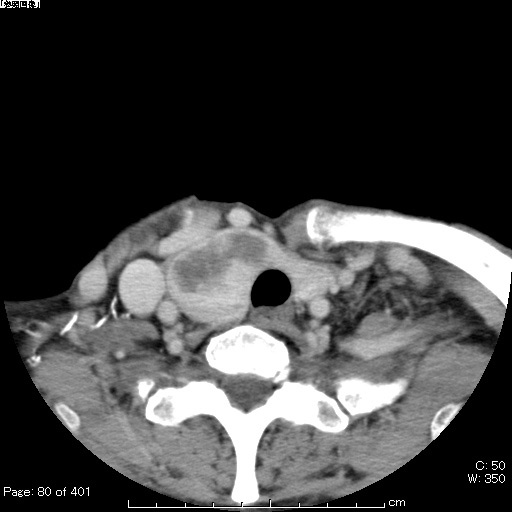

No.73症例3:60歳代女性

- 【主訴】

- 嗄声

- 【現病歴】

- 今年5月より嗄声出現。精査目的に 当院受診した。

図1 08/19頭頸部単純/造影CT

図2 08/19頭頸部単純/造影CT